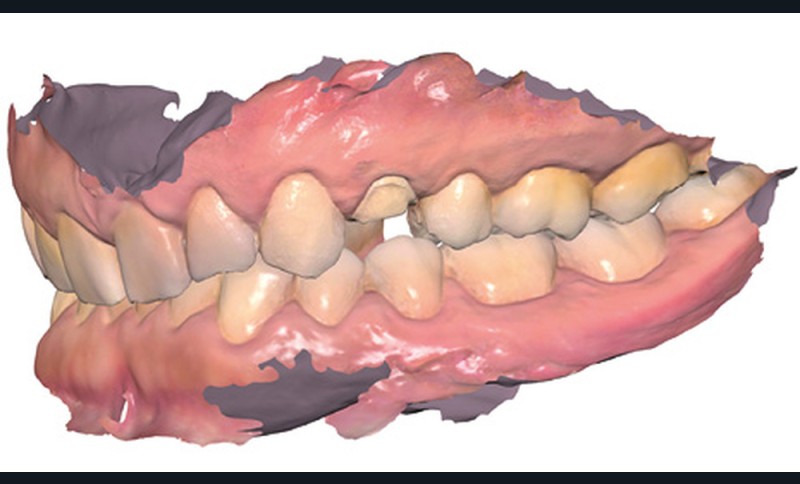

Lors de la préparation de piliers de bridge, la difficulté principale est de réussir à paralléliser correctement les piliers pour trouver un axe d’insertion pour la future prothèse. Là encore, l’empreinte optique facilite l’évaluation du parallélisme avec des outils très visuels et simples d’utilisation (fig. 8).